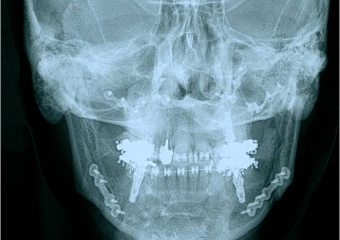

Telerradiografia frontal inicial

Telerradiografia frontal após a cirurgia